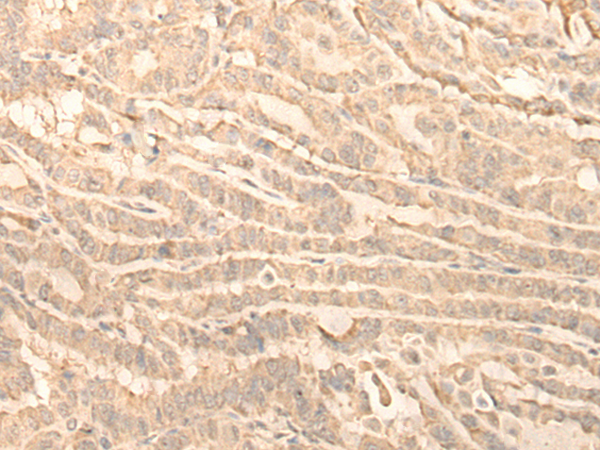

The image is immunohistochemistry of paraffin-embedded Human thyroid cancer tissue using 47192(RNF146 Antibody) at dilution 1/30. (Original magnification: ?00)